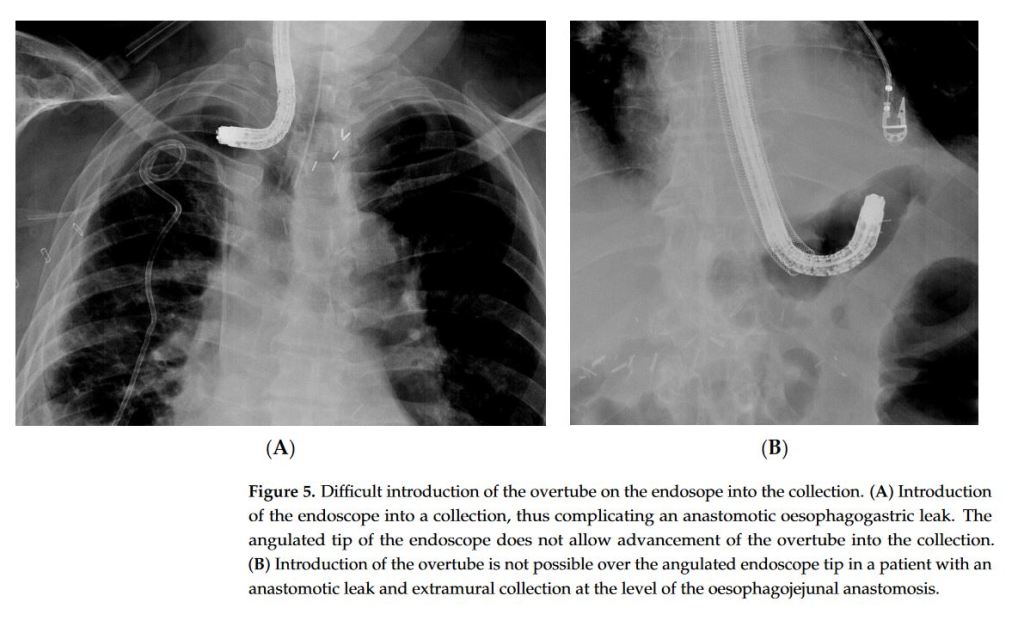

Endoscopic vacuum therapy (EVT) is a novel treatment option that is nowadays recognized as an effective and useful endoscopic approach to treat leaks or perforations in both the upper and lower gastrointestinal tract. EVT has a very good safety profile. However, it is a time-consuming endeavour requiring engagement from the endoscopist and understanding from the patient. To the unexperienced, the EVT technique may be prone to several hurdles which may deter endoscopists from using it and depriving patients from a potentially life-saving therapeutic option.”